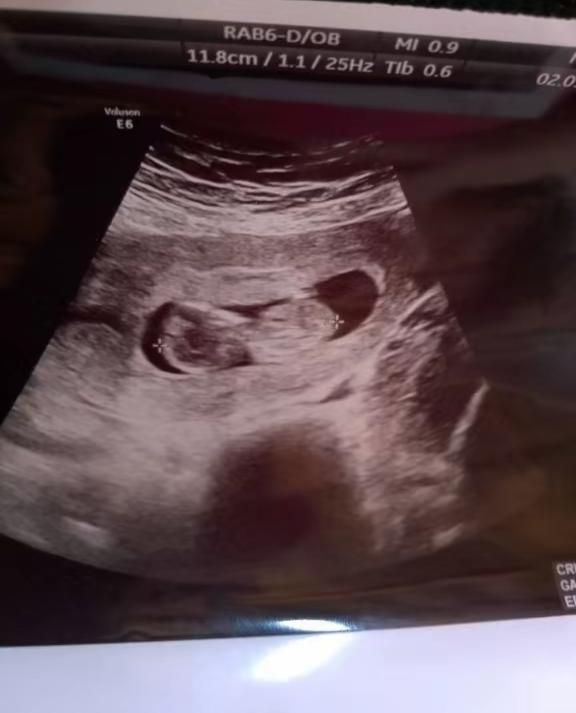

@jaskolka prikladám fotku zo dňa 2.9. a napísal mi toho 10 júna tak lebo mám veľmi nepravidelnú menštruáciu a nesedelo mu to podľa usg

Mohol byť plod už v 12tt ? Na tej fotke

No a čo sa týka fotky,.. Keby si otehotnela s tým prvým,tak by bol plod už v 15-16tyzdni vývoja,tento plod vyzerá tak na 12 týždeň, odhadom,čiže stále z toho vychádza,že adeptom na začiatku dva je druhý chlapík

Ty silou mocou asi chces,aby to bol ten prvý, však? Proste keby si otehotnela vtedy,tak by plod mal na usg toho 5.9 už okolo 15-16 týždňov,a to by vyzeral inak,bol by väčší. Aj termín pôrodu by si mala inak,ak si porodila v 38 týždni,to tiež ukazuje,že otec bude druhý muž.Jedinú odpoveď ti aj tak dá test DNA,ale možnosť,že otec je ten prvý,je prakticky vylúčená.

Teoreticky by to bolo možné,keby si mala veeeľmi posunutú ovuláciu,ale to by zasa toho 5.9 bol plod menší,nie tak na 12 týždeň vyvoja. Ono to vyzerá tak,že si mala posledný menzes 27.5 a ovulácia bola presne okolo toho 16.6. Čiže vždy z toho vychádza len ten druhý chlap.